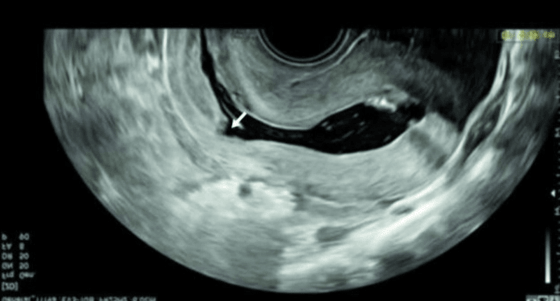

病例再现 / 02

宫腔水造影可以显示二维超声看不见的瘢痕部憩室。